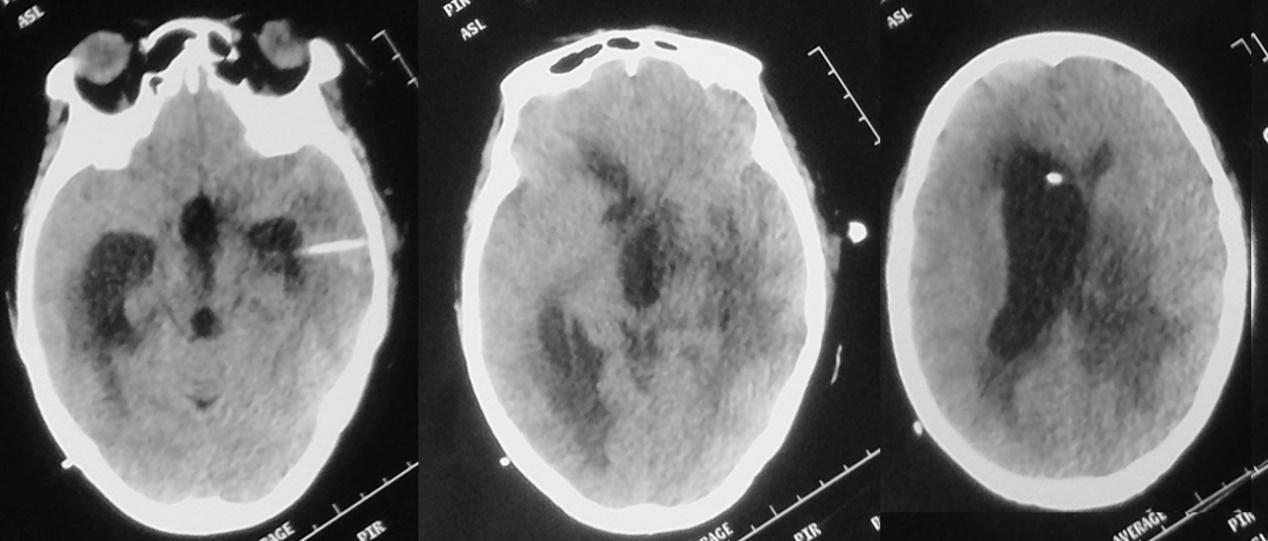

发病后21天,脑室外引流后8天,即2020年11月29日,复查头颅CT见左侧脑室较前(2020年11月22日)缩小( 图-6 ),继续抗炎及脑室外引流治疗。

图-6: 2020年11月29日头CT

脑室外引流结合抗炎治疗后第13天(2020年12月4日)和15天(2020年12月6日),患者意识仍呈嗜睡至昏睡状态,病情无明显好转,复查头颅CT见左侧丘脑病变周围水肿较前好转,但脑室仍扩张明显( 图-8、图-9 )。

图-8: 2020年12月4日头CT

图-9: 2020年12月6日头CT

患者一直呈嗜睡至昏睡状态,强刺激才能对答,仍发热,体温持续在38℃左右。于发病后29天,抗炎及脑室外引流治疗后16天,即2020年12月7日,进行了左额开颅丘脑脓肿清除术,术中经皮层造瘘口留置脑室内引流管;术后当天头CT( 图-10 )呈术后改变。

图-10: 2020年12月7日头CT

脓肿清除术后第1天,2020年12月8日,意识障碍较术前加重,呈朦胧状态,不能对答;复查头颅CT见术区少量出血,左侧脑室颞角明显扩张( 图-11 );当天紧急行左侧脑室颞角穿刺外引流术。

图-11: 2020年12月8日头CT